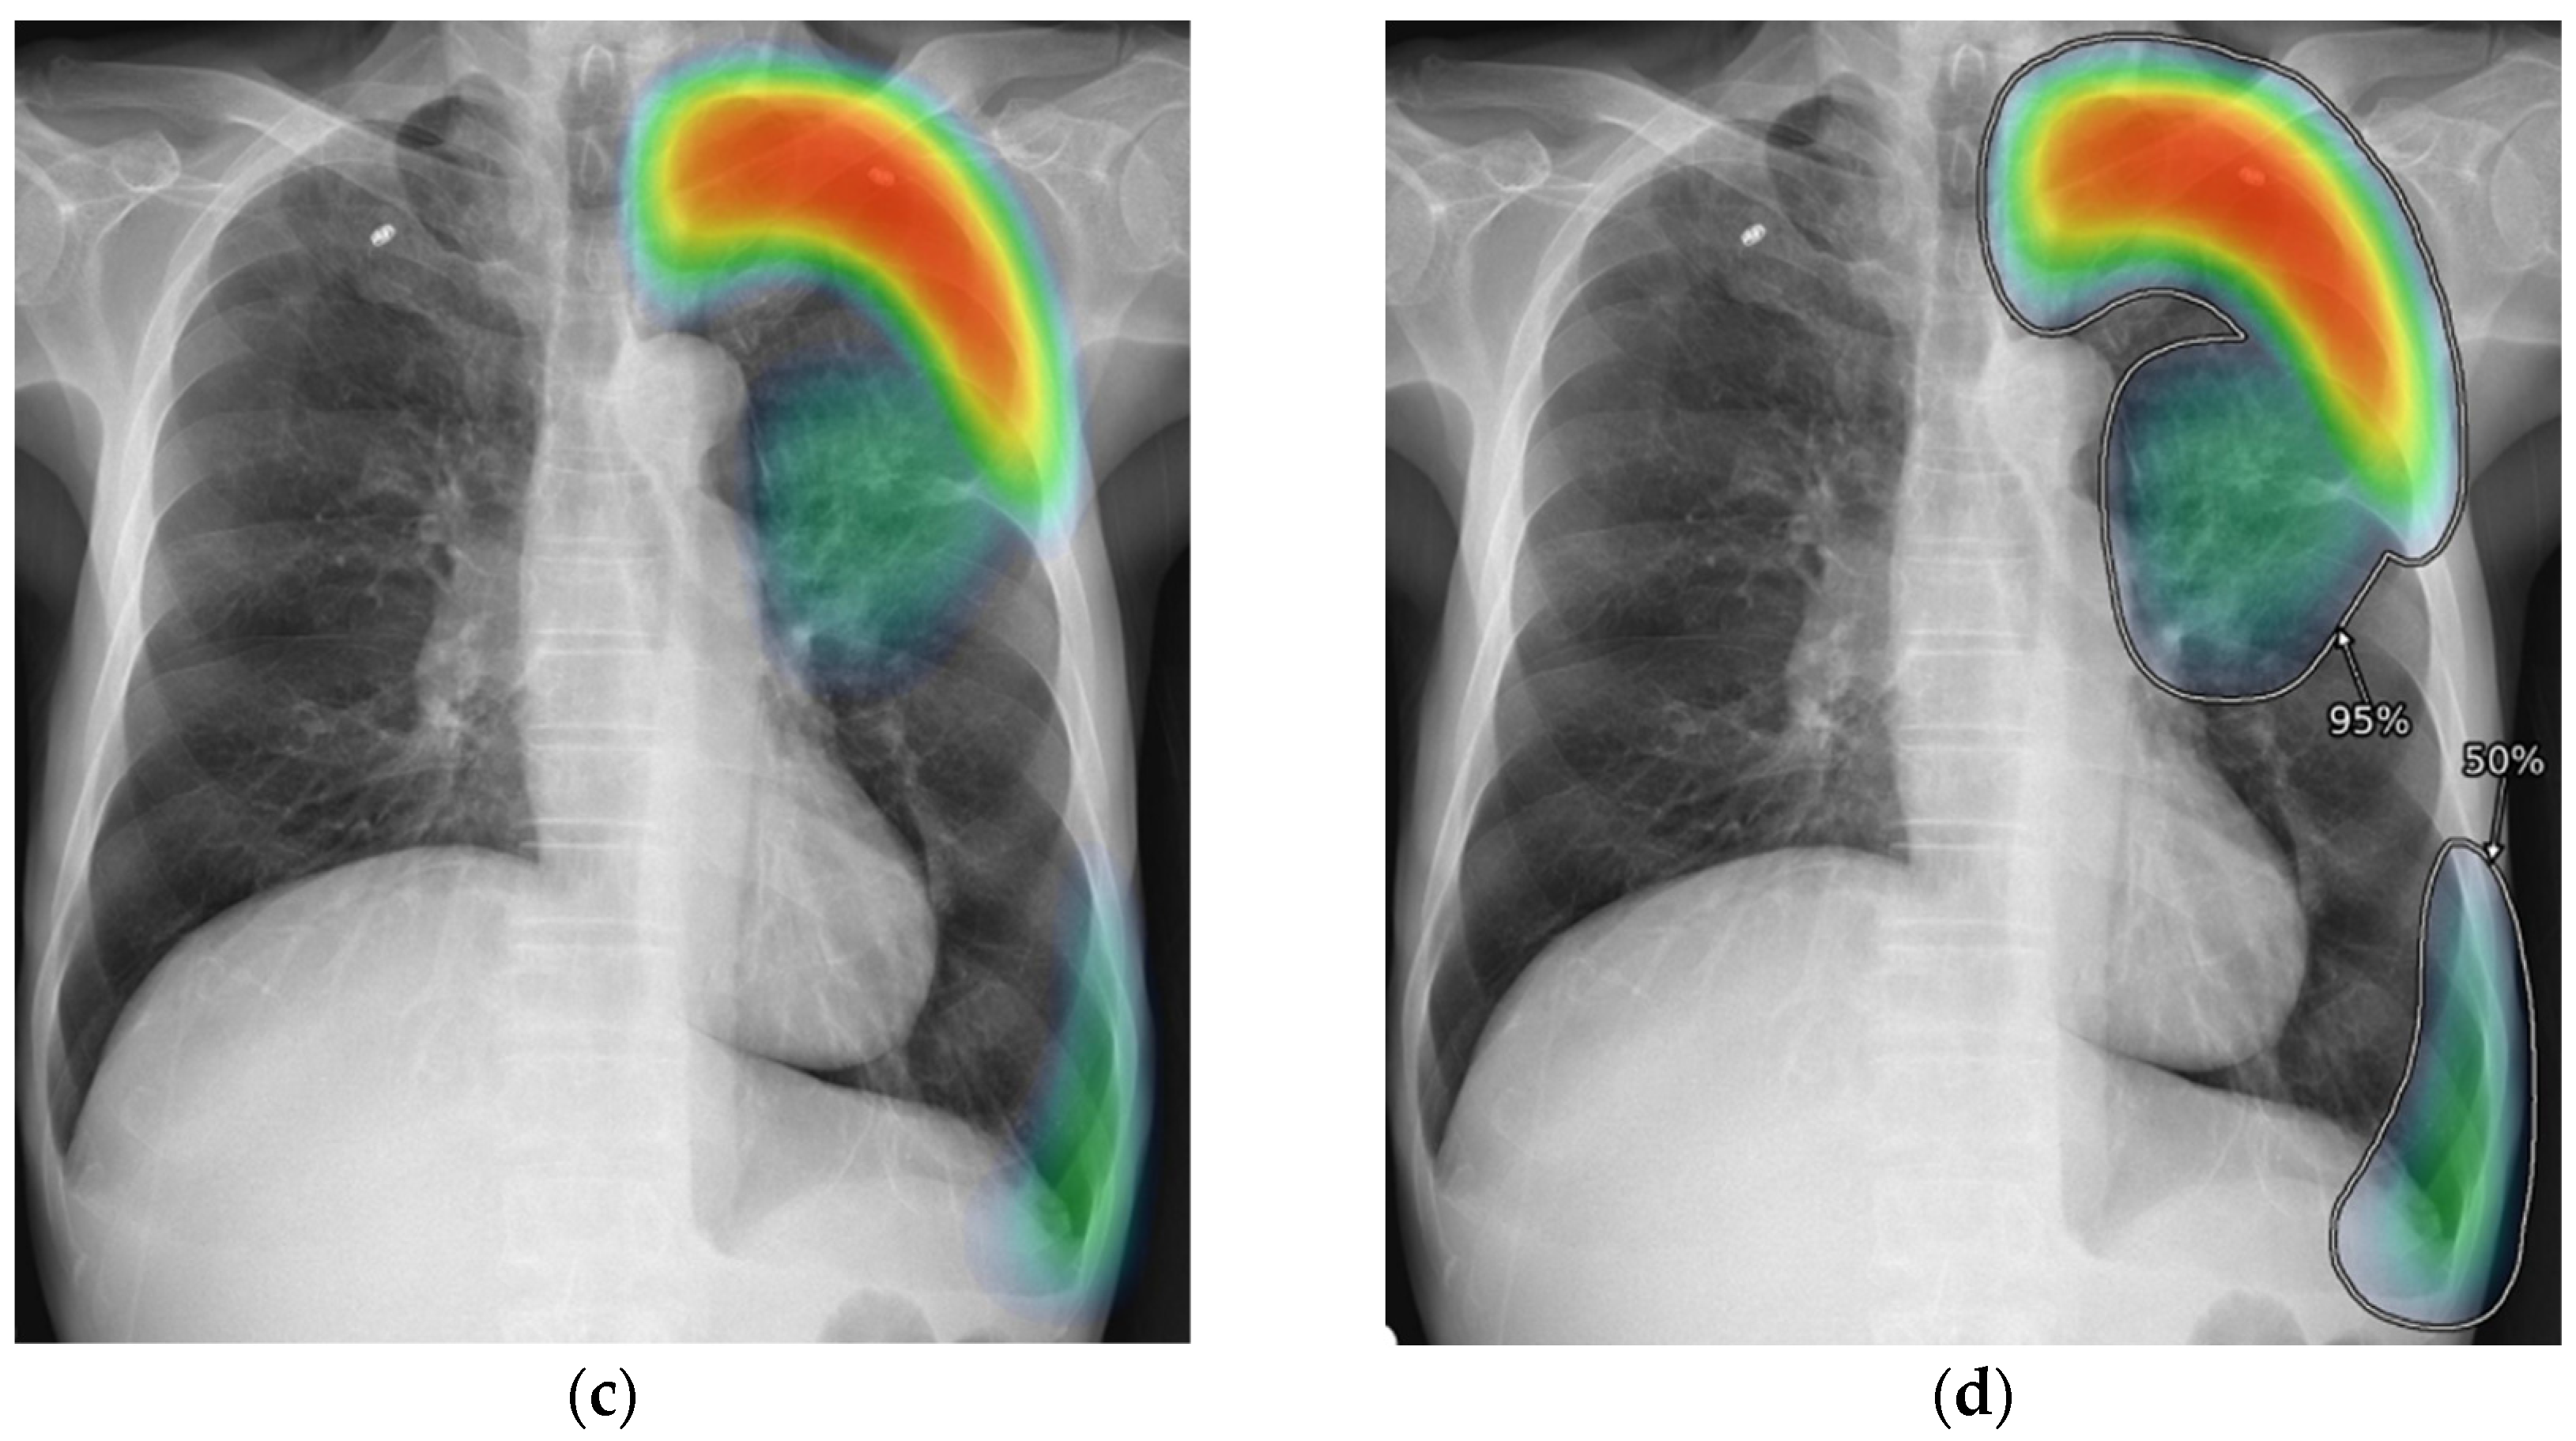

2.3. AI-CAD

2.4. Reader Test